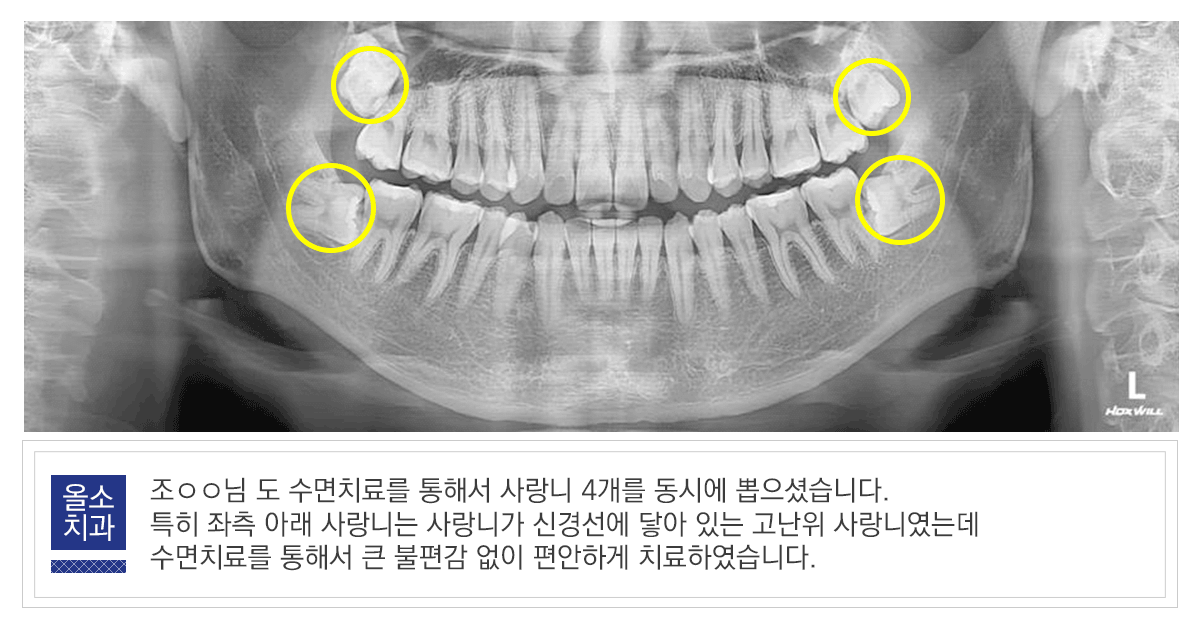

조oo.gif

사랑니는 어금니와 같은 기능을 하는 치아이지만, 다른 치아와 달리 기형으로 자라는 경우가 많고, 위축된다는 면에서 어금니와 유사한 역할을 기대하기는 한계가 있습니다. 사랑니 통증이 있을 때는 자가진단하시지 마시고, X-ray 촬영을 통해서 사랑니의 모습을 확인, 의료진의 정확한 진단을 받는 것이 중요합니다.